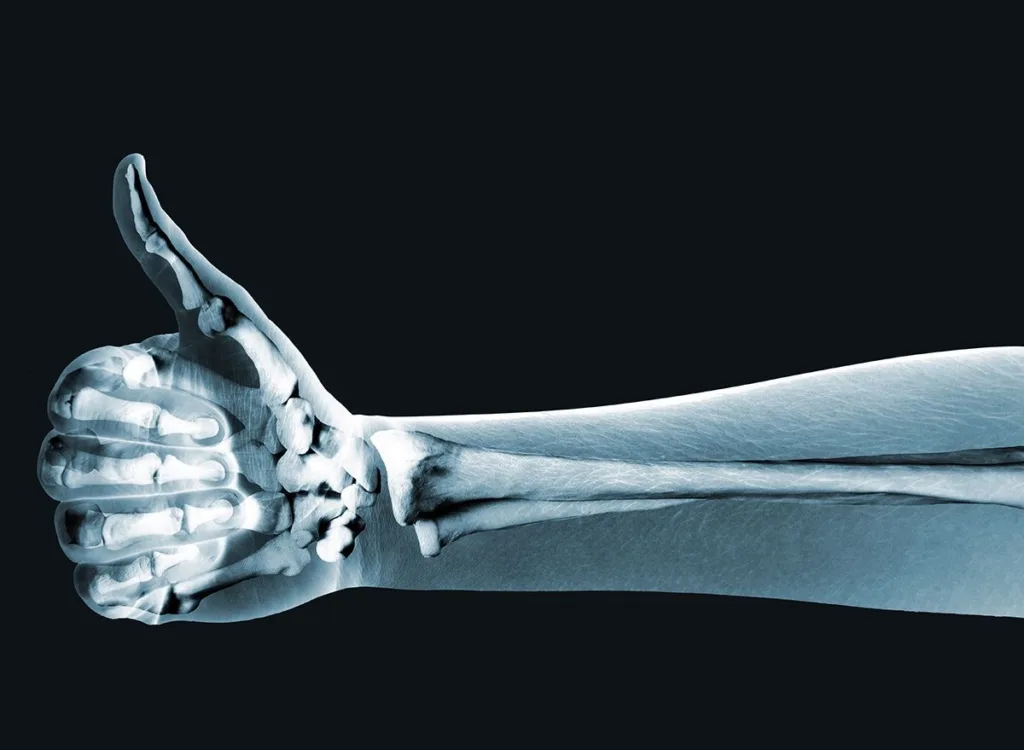

यहाँ आपकी हड्डियों को स्वस्थ रखने के 10 तरीके दिए गए हैं:

यहाँ कुछ कारण बताए गए हैं कि स्वस्थ हड्डियाँ क्यों महत्वपूर्ण हैं:

1. समर्थन और संरचना: हड्डियाँ आपके शरीर को सहारा देती हैं और आपको सीधा खड़ा रहने, चलने और दैनिक गतिविधियाँ करने में मदद करती हैं।

3. गतिशीलता में सहायक: हड्डियाँ मांसपेशियों, लिगामेंट्स, और टेंडन्स के साथ मिलकर गति को संभव बनाती हैं। हड्डियों द्वारा बने जोड़ों से शरीर को लचीलापन और विभिन्न दिशाओं में घूमने की क्षमता मिलती है।